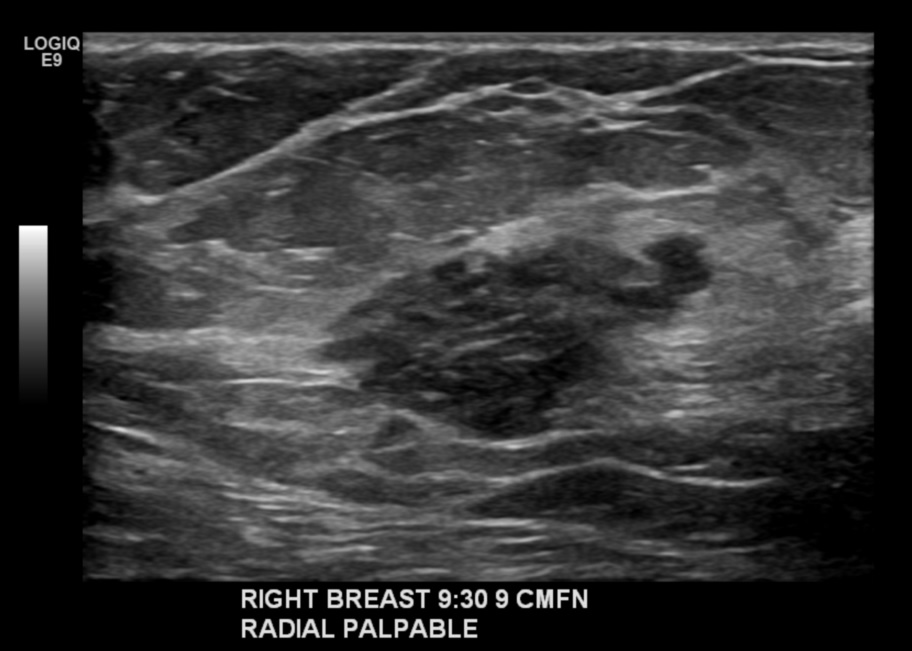

The initial diagnosis happened so fast. It was Boom! Lump. Boom! Mammogram and ultrasound. Boom! Biopsy. Boom Boom Hiss! It’s cancer, bitches.

- Breast MRI. This will give us a clue as to if Turdy has sent scouts into my lymph nodes. Why is this a big deal? Because if my nodes are clean we can probably just evict Turdy and do a round of radiation. I.e. no chemo. What’s the holdup? My goddamn menstrual cycle. [Editor Me: Yuck, are we really doing this? Writer Me: Are we going for pretty or honest? Editor Me: *sigh* Writer Me: Okay, then.] Because boobs swell and change over the course of the month, they need to pinpoint the MRI between day 7 and day 13 of the cycle. Which means that I’m supposed to call the scheduler when I get my period. So they (Boobcutter, Cappucino, and the MRI peeps) are all waiting for that to happen. And you know how being stressed out about it helps that situation. This may be even more stressful than a teenage broken condom scenario.